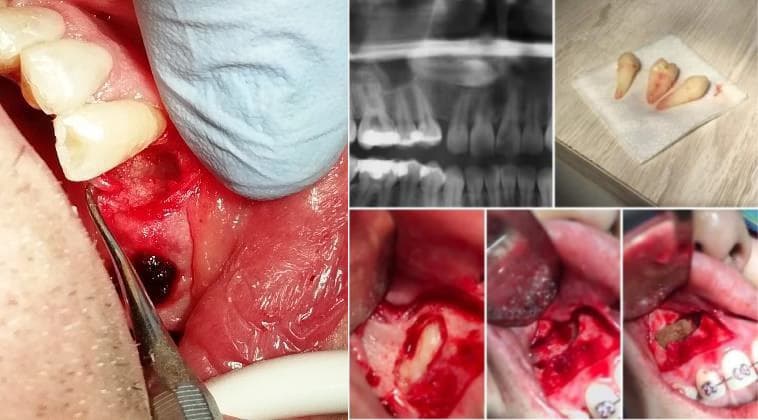

Cirugía Maxilofacial y Periodontal

El cirujano maxilofacial es el que se encarga de la reconstrucción de fracturas de la cara ocasionadas por un golpe muy fuerte, además de corregir deformidades del maxilar y la mandíbula, también es quien extrae caninos retenidos y hace cirugía de las muelas del juicio.

La cirugía periodontal se encarga de tratar infecciones avanzadas en los tejidos alrededor del diente, nos ayuda a corregir defectos óseos y en encía, además, la gingivoplastia y el alargamiento de corona nos permite mejorar la estética dental en nuestros pacientes.